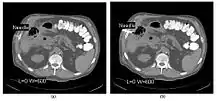

CT Fluoroscopy (CTF) has also been referred to as Continuous CT or Real-Time CT since it involves generating tomographic images at sufficiently high frame rates to allow guidance of needle placement in small or deep-seated lesions. Applications can include biopsy of thoracic lesions, biopsy/drainage of pelvic lesions, vertebroplasty and drainage/aspiration of intracranial haematomas. The advantages of CTF include increased target accuracy and reduced procedure times[45].

The major difference to a conventional CT system is that high speed reconstruction techniques are applied, and that an operator panel, exposure footswitch and image monitor are installed in the scanning room for use by the interventionist. Controls are generally available for table movement, gantry tilt, laser grid definition and fluoroscopic factors. The other significant operational change relates to the choice of tube current which is typically 30-50 mA in CTF. This should be compared with typical screening currents used in conventional fluoroscopy of up to 5 mA, so that CTF can be regarded as a high dose procedure. In this context, additional beam filtration can be introduced automatically for CTF procedures to reduce patient exposure by up to 50%, for example. Furthermore, the use of protective gloves and needle holders can reduce the radiation exposure to the hands of the interventionist.

Fig. 7.15.11: CT Fluoroscopy images acquired at 80 kV, 56 mAs, and 5 mm slices are noisy in comparison with diagnostic images. In (a) the needle, barely in slice plane, is shown striking a rib whilst in (b) it is in the soft tissue.

The value of N is typically 30o, 45o or 60o, with frame rates of 12, 8 and 6 frames per second, respectively. In the case of 60o updates and 6 frames per second, the delay between each image is 0.17 seconds. A Last-Image-Hold (LIH) technique can be used while the image is being updated with the resulting time lag being considered by the interventionist in terms of biopsy technique. Example images are shown in Figure 7.15.11. The display of three adjacent slices of thickness 5 mm with MDCT scanning can be used to improve visual feedback to the interventionist as the needle progresses. In addition, multi-planar reconstructions (MPR) and volume rendered 3D images can be used to enhance fine control.